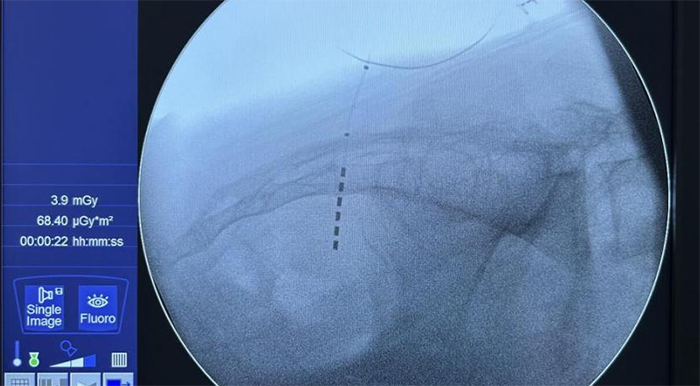

图为新型6触点电极成功植入患者体内